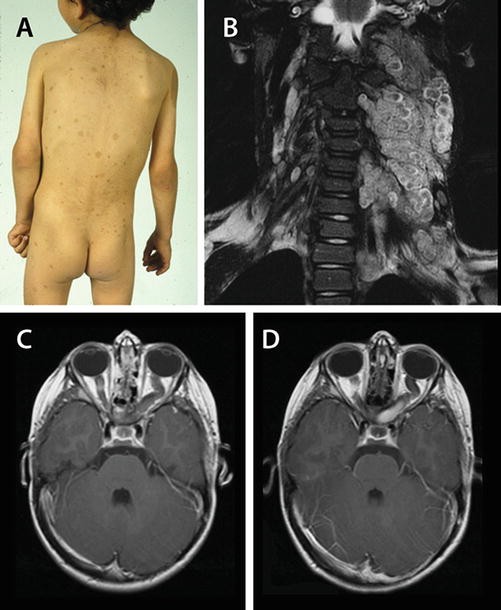

Management Of Orbital Rhabdomyosarcoma In A Child With Li Fraumeni Syndrome Journal Of American Association For Pediatric Ophthalmology And Strabismus Jaapos